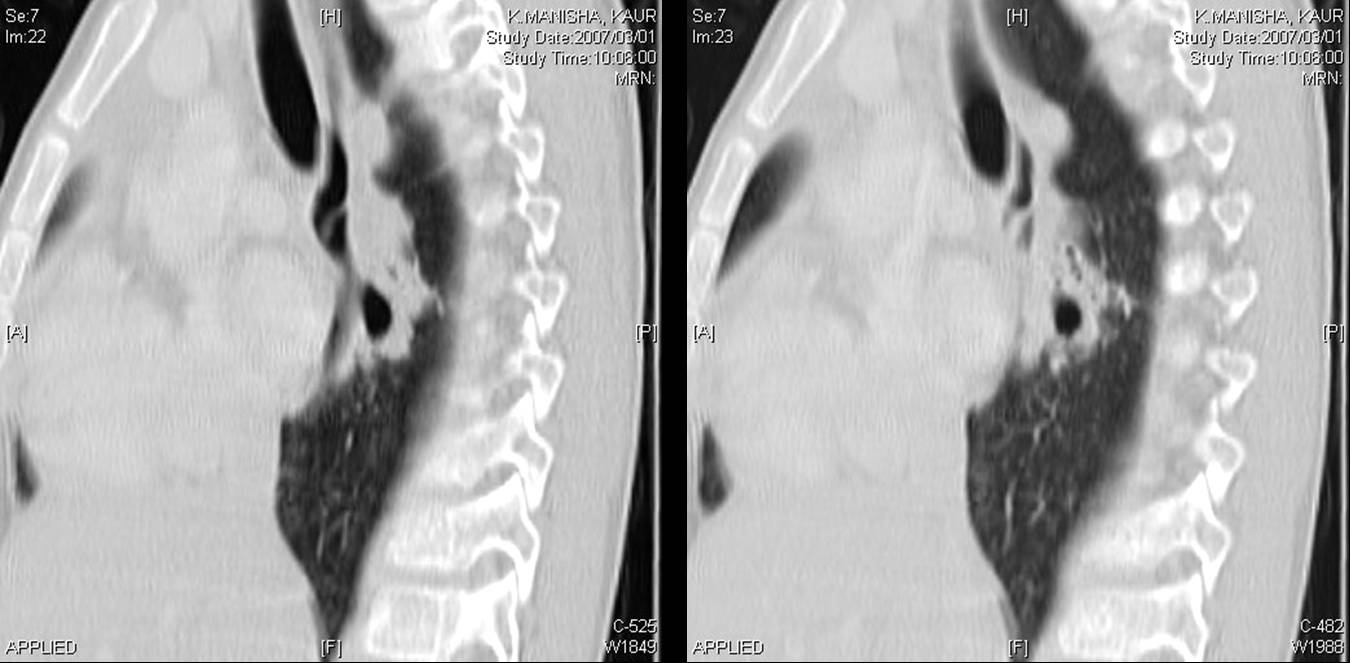

A CT scan of chest was done.

The following screen shows the images from the Chest CT.

| Figure 4-a | Figure 4-b | Figure 4-c |

| Figure 4-d | Figure 4-e | Figure 4-f |